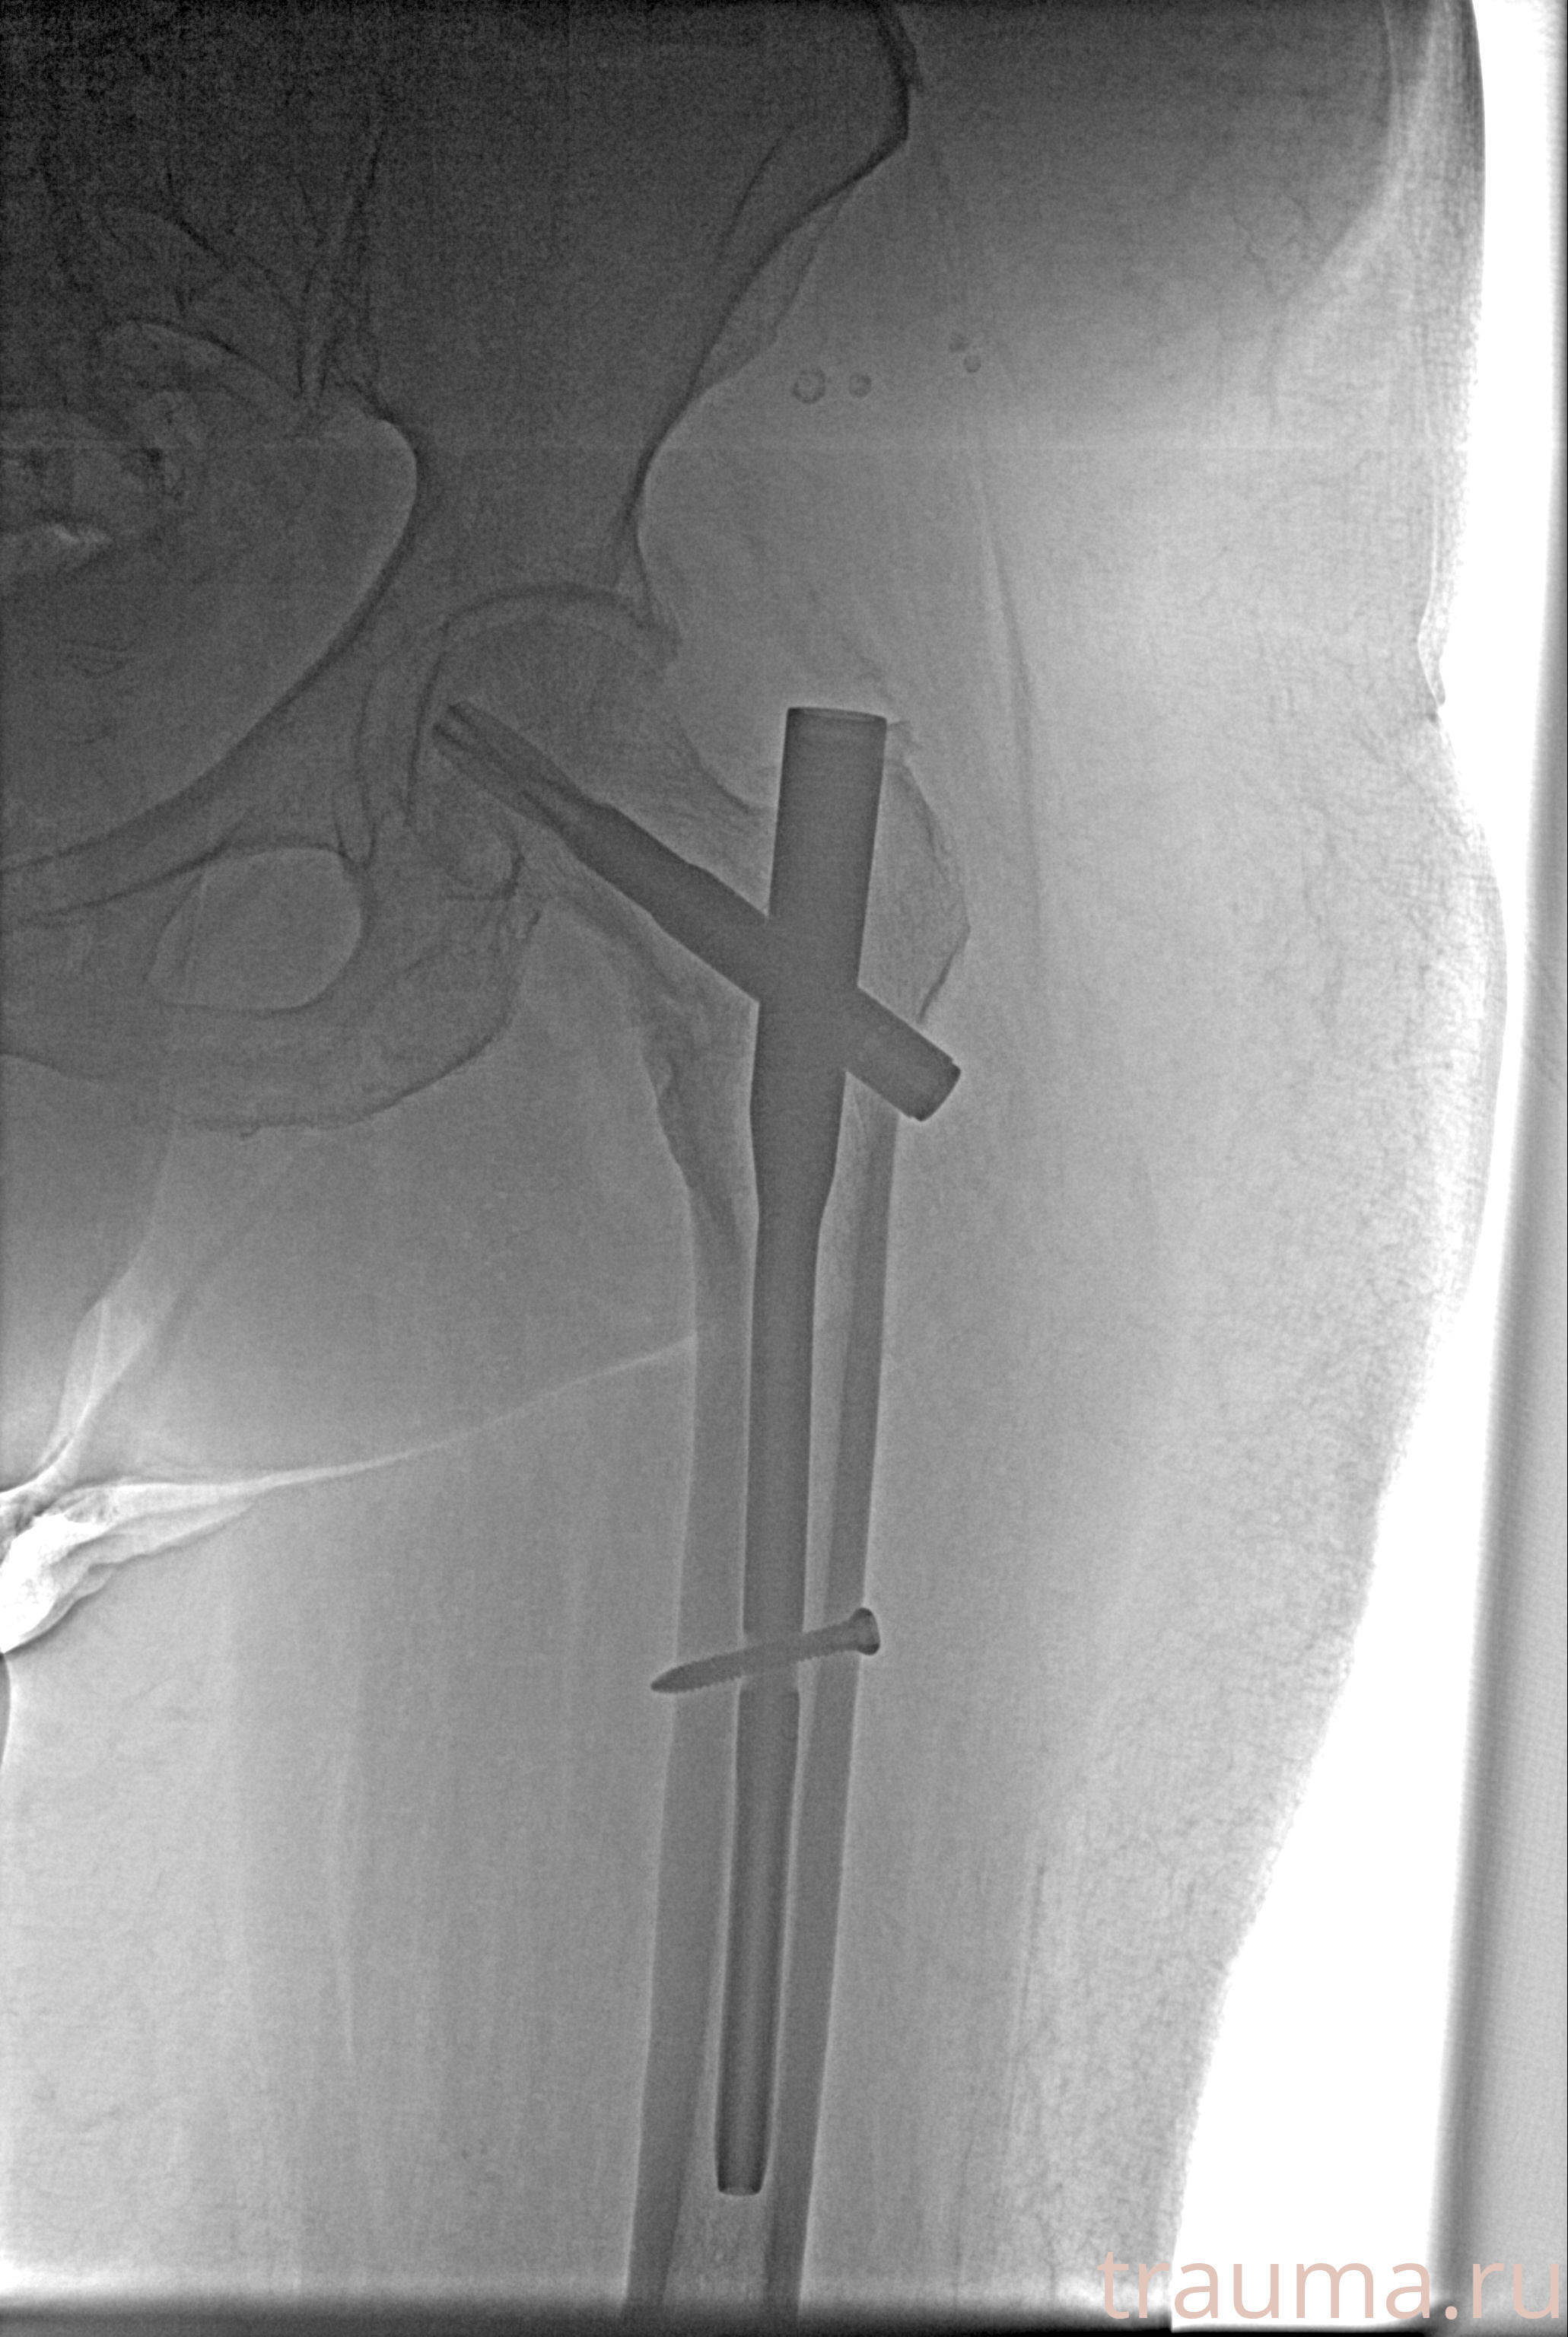

Рентгенограммы

Рентген на дому: по вашему адресу приезжает врач-рентгенолог, травматолог-ортопед с мобильным рентгеновским аппаратом, проводит диагностику травмы или заболевания, делает необходимые рентгенограммы, дает рекомендации по дальнейшему лечению. Получить качественные снимки в домашних условиях возможно благодаря уникальной методике, разработанной МосРентген Центром для института  Склифосовского